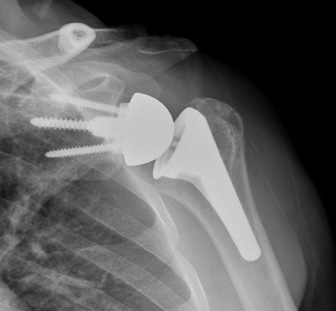

Shoulder replacement surgery, also called shoulder arthroplasty, involves removal of damaged portion of bone and replacement with implants made of metal and plastic.

- Anatomic Total Shoulder Replacement – Your surgeon will remove both damaged parts of the joint (humerus head and glenoid) and replace with the artificial implants retaining the normal ball and socket orientation of the joint.

- Reverse Total Shoulder Replacement –Reverse shoulder replacement is a commonly performed procedure where normal anatomical orientation of the ball and socket joint is reversed to socket and ball orientation providing satisfactory function in a rotator cuff deficient shoulder. Here, your surgeon will remove both parts of the joint and attach ball to the shoulder blade and socket to the upper arm bone.